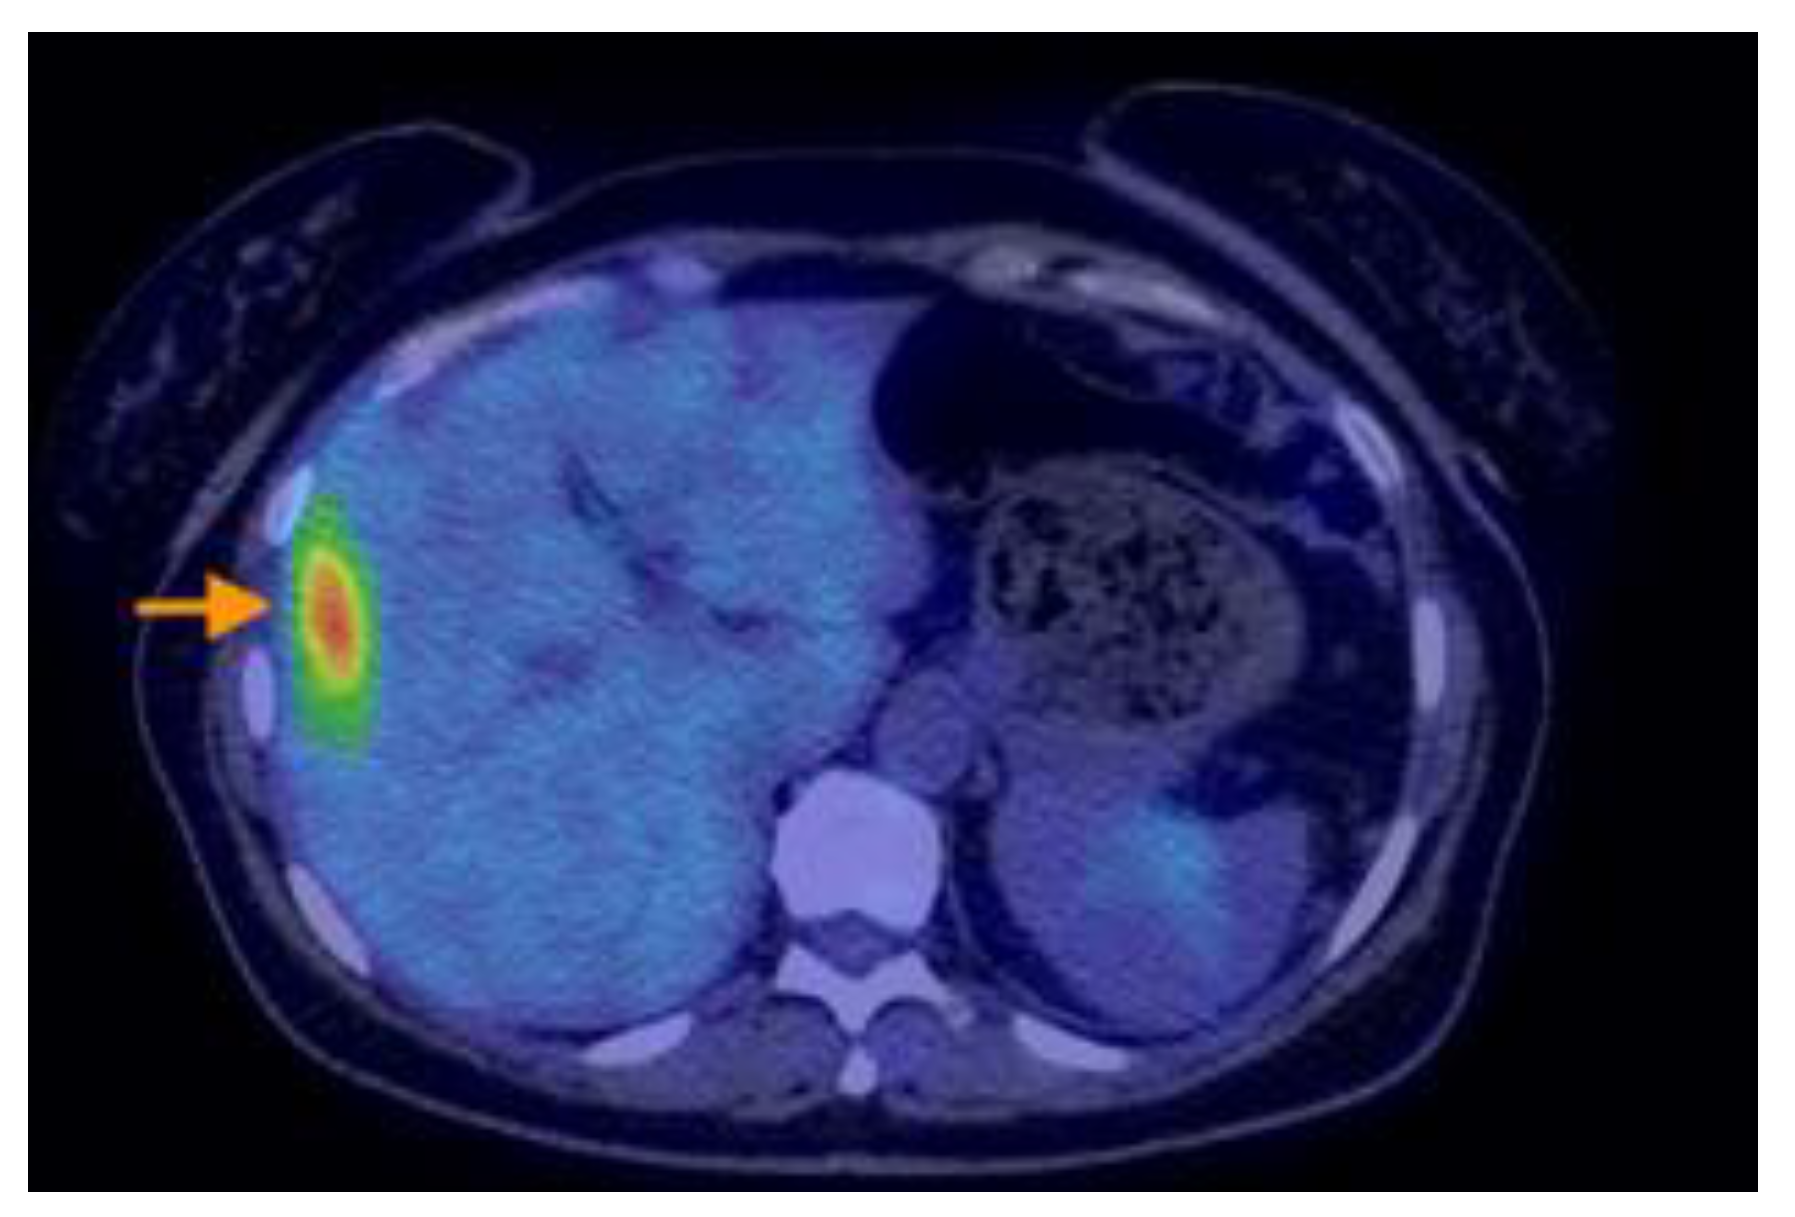

3.2.3. Imaging Findings, Diagnosis, and Differential Diagnosis